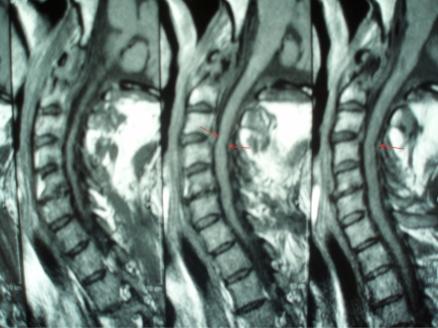

Dialysis-related spondyloarthropathy is a rare cause of spinal deformity and cervical myelopathy. Optimal management of cervical spine spondyloarthropathy often requires circumferential reconstructive surgery, because affected patients typically have both the anterior column and the facet joints compromised. The occasional presence of noncontiguous or "skip lesions" adds an additional level of complexity to surgical management, because decompression and fusion in an isolated segment of neural compression can worsen spine deformity by applying increased stress to adjacent cervical spine segments. We report two cases of hemodialysis patients who presented with cervical myelopathy and initially had anterior cervical discectomy or corpectomy. Because symptoms recurred due to hardware failure, both patients required posterior spine fusion as well. In retrospect, because of the hardware failure, both of these patients might have benefited from a circumferential (combined anterior and posterior) cervical spine reconstruction as their initial treatment.

透析相关性脊柱关节病是脊柱畸形和颈椎脊髓病的罕见病因。颈椎脊柱关节病的最佳治疗通常需要进行环形重建手术,因为受影响的患者通常前柱和小关节均受损。偶尔出现的非连续性或“跳跃性病变”增加了手术治疗的复杂性,因为在孤立的神经受压节段进行减压和融合会因对相邻颈椎节段施加更大压力而加重脊柱畸形。我们报告了两例血液透析患者,他们均表现为颈椎脊髓病,最初接受了颈椎前路椎间盘切除术或椎体次全切除术。由于内固定失败导致症状复发,两名患者均还需要进行后路脊柱融合术。回顾来看,由于内固定失败,这两名患者最初若接受环形(前后联合)颈椎重建术可能会受益。